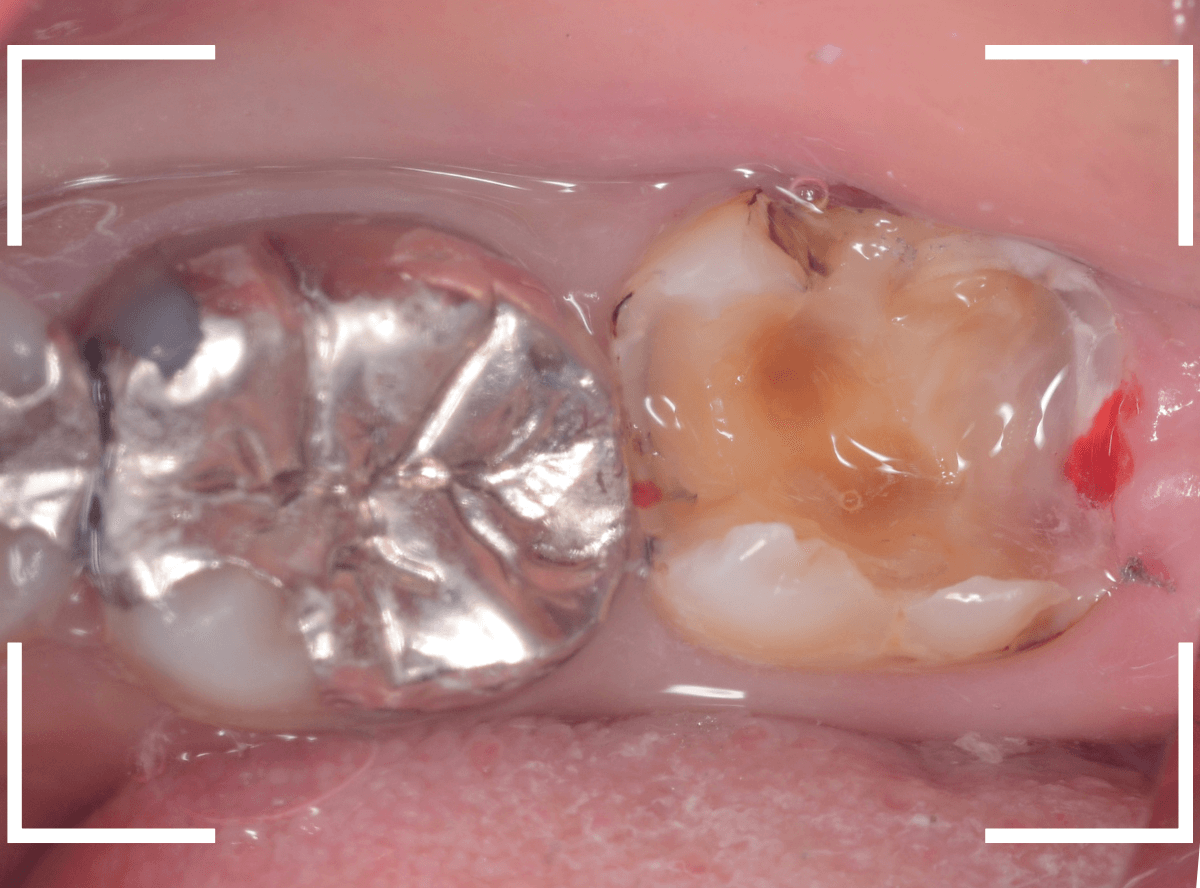

Case.15 歯の側面のレジンの中のわかりづらい虫歯

検診で、金属のつめ物のの中と、歯の側面に虫歯が見つかった方です。

まずは、手前(左)側の治療です。

こちらが、お口の中を見たところです。

〇部の中に虫歯があると思われます。

今回のように、金属のつめ物やレジン治療をしてある歯の側面の虫歯の診断はわかりづらく、難しいです。

金属のつめ物を外したところです。

この白いセメントの中に虫歯があると思われます。

セメントを除去したところです。

赤く染まっている部分が虫歯です。

真っ赤ですね(^^;)

まだ薄く染まっています。

もう少し除去する必要があります。

全ての虫歯が取れました、かなり深い神経まで近い虫歯でした。

金属のつめものをを外します。

つめものの下で虫歯になっていたせいで、虫歯と一緒に手前側のエナメル質がガリっと欠けてきました(><)

前の治療でつめたセメントを外しつつ、虫歯治療を行います。

写真ではわかりづらいですが、赤く染まった部分を中心に、虫歯がかなり広がっています。

虫歯を全て取り切ったところです。

神経スレスレの部分まで広がった虫歯で、最後は神経に触らないようにエキスカを使った、手探りでの虫歯治療になりました。